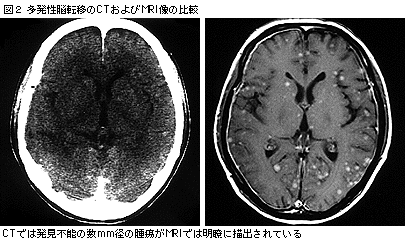

しかしながら,CTにて診断可能な病巣は直径5mm程度までであり,それ以下の病巣は見逃され,1つの病巣に対する治療が終了したころに,別の病巣が明らかになることもまれではなかった。これに対し,MRIはCTで発見不能な小さな初期病変までも発見可能である(図2)。

転移性脳腫瘍の画像としては,CT, MRIいずれでも造影剤にて増強される円形の病変として描出されることが多く,大半の病巣は周囲に広範な脳浮腫を伴う。原発臓器によっても画像上の特徴があり,肺腺がんの脳転移ではリング状の病変,扁平上皮がんでは内部に壊死に伴う不規則な低吸収域を持つ病変として描出されることが多く,腎がんでは造影剤にて一様に強く増強される円形の像として,乳がんでは頭蓋骨転移やがん性髄膜炎による脳表に沿った病変として描出されることが多い(図3)。